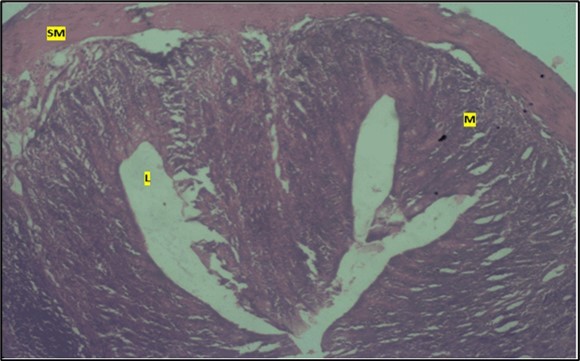

Histological examination of the small intestine result in control animals revealed a normal architecture with the red pulp and white pulp with no pathological observation Figure 2. Administration of Abelmoschus esculentus at low dose shows an increased cellularity with numerous cells in the Mucosa and the villi projecting towards the lumen. Focal metaplasia of mucosal cells alongside villous disruption was also observed (Figure 3). The high dose group showed normal cellular architecture with no villous disruption (Figure 4).

Figure 4.High dose showing a normal mucosa (m) with villi (v) projecting towards the lumen(l) and underlying smooth muscle layer (sm). No pathology seen